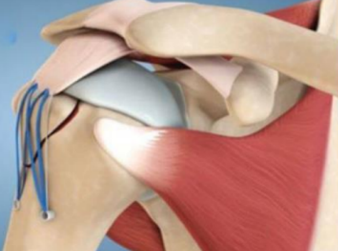

解决方案:带线锚钉“缝线桥技术”

对于需要手术的病例,带线锚钉技术已成为金标准,其目标是实现解剖复位(把骨块放回完美位置)和牢固固定(让骨头顺利愈合)。

内排锚钉:在肱骨头的关节面边缘(骨折线下方),置入第一枚带线锚钉。锚钉牢牢抓住骨质疏松的骨松质,高强度缝线则留在外面

过线固定:将锚钉的缝线以特定方式穿过附着在骨块上的肩袖肌腱-骨结合部,将骨块束缚住

外排锚钉:将内排锚钉的两根缝线尾端,分别以一定张力拉向骨块下方更远处的肱骨干皮质

加压锁定:将这两根线穿过外排锚钉的卵圆孔。缝线在骨块上方形成了一个具有加压作用的“桥”,敲击植入外排锚钉,将骨块牢牢地压在下方的骨折床上